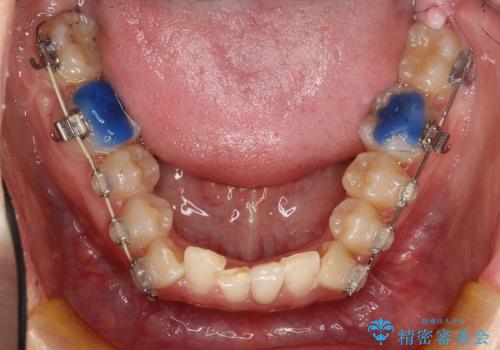

ハーフリンガル ワイヤー矯正による非抜歯・過蓋咬合の治療

- 非抜歯、大臼歯遠心移動による臼歯関係の是正・過蓋の改善をハーフリンガル・ワイヤー矯正にて計画した。

しかし、諸々の理由でマウスピース矯正をおこなえない場合、本例のようにワイヤーを用いて治療することも可能ですが、そもそも装置が歯につかないため、非常に大変な労力を費やすことになります。